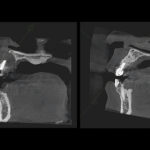

定期検診時に、患者様に症状はなかったものの、レントゲン検査で大きな骨の欠損が発見されました。原因を調べたところ、過去の大きな虫歯治療による神経の壊死(えし)と、その影響で歯の根の周りの骨が溶け、さらに歯周病との合併により複雑化した状態であることが判明しました。

まず、通常の根管治療(根の中の治療)から始めましたが、十分な改善が見られませんでした。そこで、より踏み込んだ治療として「意図的再植術」と最新の「歯周組織再生療法」を組み合わせた治療を選択しました。

具体的には、一時的に歯を抜去し、口腔外で歯の根の先端を精密に治療。その際、失われた骨を再生させるため、特殊な再生材料を併用しました。この再生材料は、体内で新しい骨の形成を促進し、歯周組織の回復を助ける働きがあります。

処置から2年が経過した現在、失われていた骨は良好に再生し、歯の機能も問題なく回復しています。定期的な経過観察でも安定した状態が確認できています。